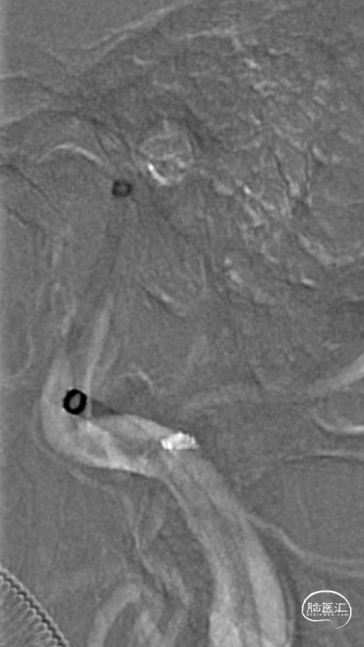

术前造影:

造影显示RICA:C1段起始部闭塞,残端呈锥形,TICI分级0级;RMCA未显影,远端由RACA经皮层支少量代偿,ASITN分级1-2级。

将Catalyst7 132中间导管经导引导管送至于RICA C1段起始部闭塞处,采用ADAPT技术自C1段至C4段反复抽吸取栓,取出大量暗红色血栓。

手推冒烟见RICA C1-C5段显影,C5段以远闭塞。将Pro-18微导管在Synchro(0.014×200mm)微导丝引导下送至RMCA M2段,微导管冒烟示远端血流通畅。将Trevo XP(4×20mm)取栓支架于M1段远端向RICA末端释放,采用SWIM技术取栓1次,并同时将中间导管送至颈内动脉末端抽吸。抽出数枚暗红色血栓。

造影见RICA再通,RMCA M1段近端重度狭窄,约90%。

观察10分钟后,狭窄较前加重,局部不规则充盈缺损。术中即刻DynaCT未见造影剂染色。